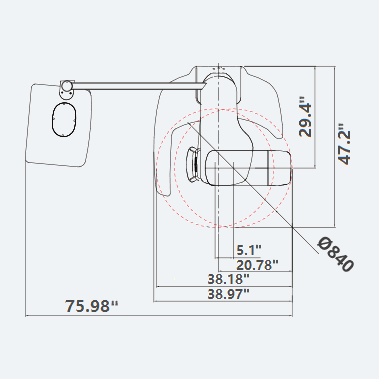

| TUBE VOLTAGE/CURRENT | WEIGHT | DIMENSIONS |

|---|---|---|

| 60 ~ 99 kV / 4 ~ 10 mA | With Ceph unit : 120 kg (264.5 lbs. – without Base) | With Ceph unit : 75.99 in (L) x 47.24 in (W) x 90.55 in (H) |

| TOP VIEW | FRONT VIEW | |

|---|---|---|

|

PaX-i RC (Rapid Ceph) |

|

|